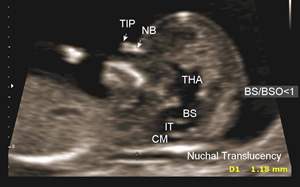

اره دیگه ۱۱هفته ....مشخص نیس ؟؟؟امروز نوبت ان تی دارم نشستم نوبتم شه😀😀